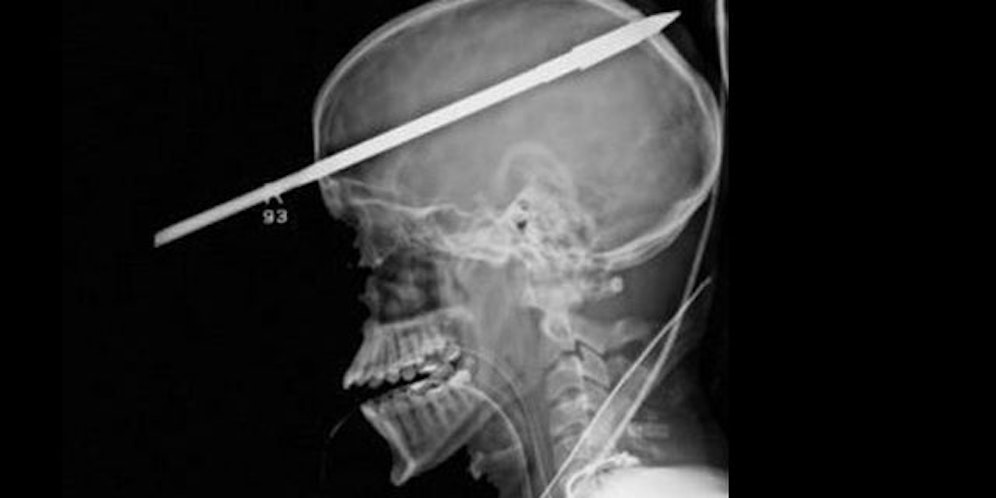

Ein 16 Jahre alter Schüler aus den USA hat einen Harpunenschuss in den Kopf überlebt. Der Jugendliche war vor zwei Wochen beim Speerfischen von einem Freund mit einer Harpune im Kopf getroffen worden. Er entging nur knapp der Erblindung.

Der spitze Pfeil trat fünf Zentimeter über seinem rechten Auge ein und am Scheitel wieder aus. Ärzte des Jackson Memorial Hospital in Miami konnten die Harpune Anfang Juni in einer riskanten, dreistündigen Operation entfernen. Um ihren Sohn zu schützen, hatten die Eltern bisher jegliche Meldungen über den Vorfall untersagt. Das Krankenhaus berichtete erst jetzt über den Vorfall.

Der 16-Jährige hatte großes Glück. "Es wurden keine lebenswichtigen Bereiche im Gehirn getroffen und auch keine großen Blutgefäße zerstört", sagte der zuständige Neurochirurg . 91 Zentimeter des Speers hatten aus dem Kopf des Patienten herausgeragt.

Bevor eine Röntgenaufnahme gemacht werden konnte, wurde der Speer mit Hilfe eines Bolzenschneiders auf 45 Zentimeter verkleinert. Erinnern kann sich der Jugendliche an den Unfall nicht. Die nächsten zwei bis drei Monate wird er im Krankenhaus verbringen.